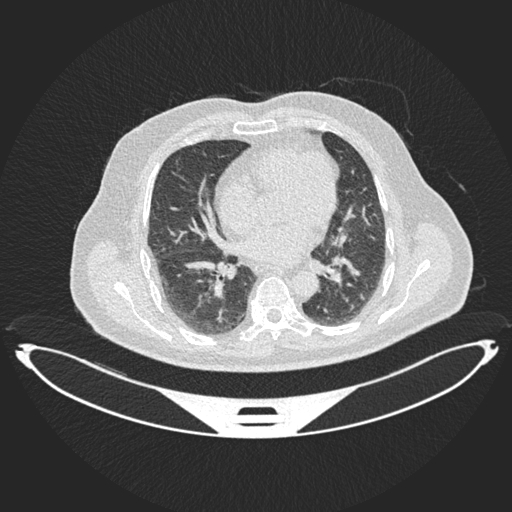

Analyzed Image

b.jpg

Uploaded: 2025-08-03 04:59:10Best Model Result

Malignant

Confidence: 65.9%

Model: DenseNet121

Ensemble Prediction

Confidence: 52.4%

Average of all modelsModel Predictions Comparison

ResNet50

Malignant:

40.4%

Normal:

ConfidenceDenseNet121

65.9%

ConfidenceEnhancedCNN

51.0%

29.4%